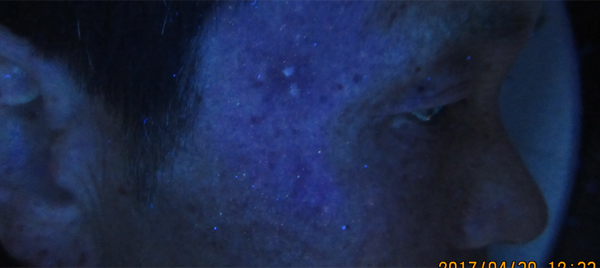

刚来院时,发病2个月,WOOD灯下白斑面积约1元硬币大小,呈圆形,边界清晰。

治疗2周后,白斑面积明显缩小,WOOD灯下面积小于目测面积,白板中出现小黑点。

治疗4周后,白斑在WOOD灯下只剩2个小点,与周围皮肤界限不明显,白点颜色淡。

治疗6周后,白斑已经消失不见,日光下肉眼几乎看不出复色不同,临床恢复。